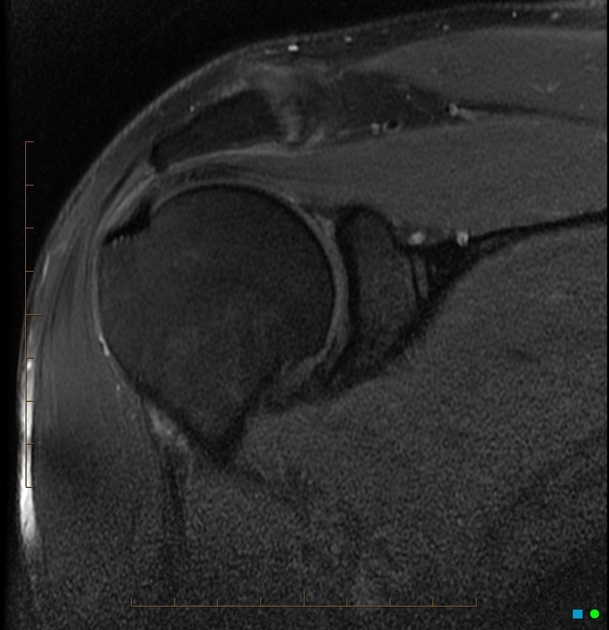

What does this FS PD MRI demonstrate?

High signal is seen extending into the superior labrum, and tracking into the labrum (and sometimes into the biceps tendon).

This is in keeping with a tear within the superior labrum, known as a superior labral anterior posterior tears (or SLAP tears).

The tear involves the labrum superiorly, where the long head of biceps tendon inserts.

Unlike Bankart lesions and ALPSA lesions, they are not associated with shoulder instability.